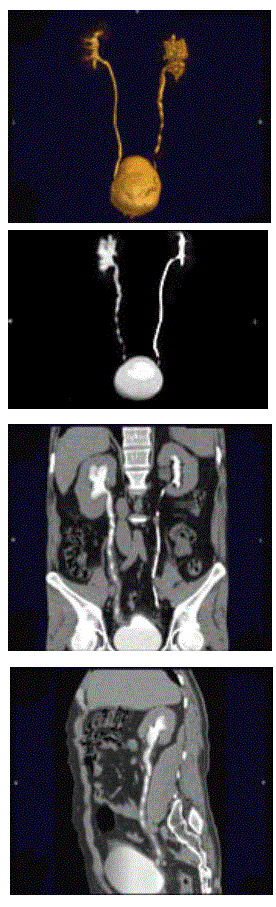

问题 男,47岁,腰痛、腰胀2个月余伴低热、乏力,如影像资料所示,下列哪项说法正确( )

选项 A、考虑为右输尿管占位病变 B、考虑为右输尿管结核 C、右侧输尿管多发性生理性狭窄 D、右侧肾盂轻度积水 E、右侧输尿管多发性狭窄,呈"串珠样"改变

答案 BDE